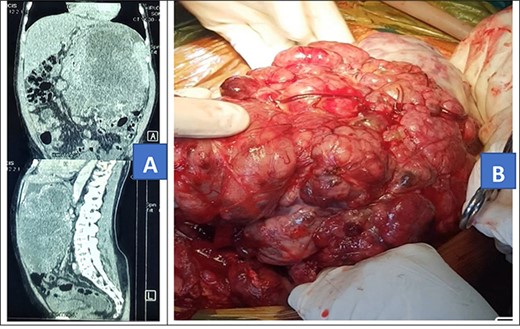

A 46-year-old African male was admitted with history of progressive weight loss and abdominal distension for 7 months. He had no history of abdominal pain, diarrhea of constipation. He, however, reported a history of on-and-off evening fevers. In review of systems, he had a history of swelling of left lower limb and had been on tabs rivaroxaban 20 mg once daily as treatment for deep venous thrombosis diagnosed 5 months prior. Rivaroxaban was stopped 24 hours prior to surgery and then continued post-operatively to complete 6 months of treatment. On examination, he had gross abdominal distension with a firm mass arising from the left lower quadrant. He also had swelling of the left lower limb with darkening of the overlying skin. Other systemic examinations we unremarkable. Prior to admission, he had done an abdominal CT scan that showed a huge mixed density soft tissue intra-abdominal mass exerting pressure on surrounding viscera (Fig. 3A). Fibrosarcoma diagnosis had been confirmed by US-guided biopsy and histology. The patient received neo-adjuvant chemotherapy, intravenous doxorubicin 100 mg with intravenous mesna 1000 mg in 100 ml of normal saline and intravenous ifosfamide 9500 mg in 3 l of normal saline with intravenous mesna 2375 mg in 1 l of normal saline every 21 days, four cycles of chemotherapy prior to referral for surgery. Investigations, including complete blood count, renal function tests, liver function tests and prothrombin time, were all grossly normal and the patient was scheduled for cytoreductive tumor resection.

Intra-operatively, a giant 40 × 35 × 12 cm liposarcoma measuring 10.1 kg was found involving the left ureter (Fig. 3B). The transverse colon, descending colon and sigmoid colon were attached to the anterior part of the mass and the rectum was displaced to the right. Other abdominal viscera were normal. The mass was mobilized from the colon. The entire mass en bloc, including the left ureter, were excised (Fig. 4). Then, the left to right ureteroureterostomy with a Double-J stent insertion done.